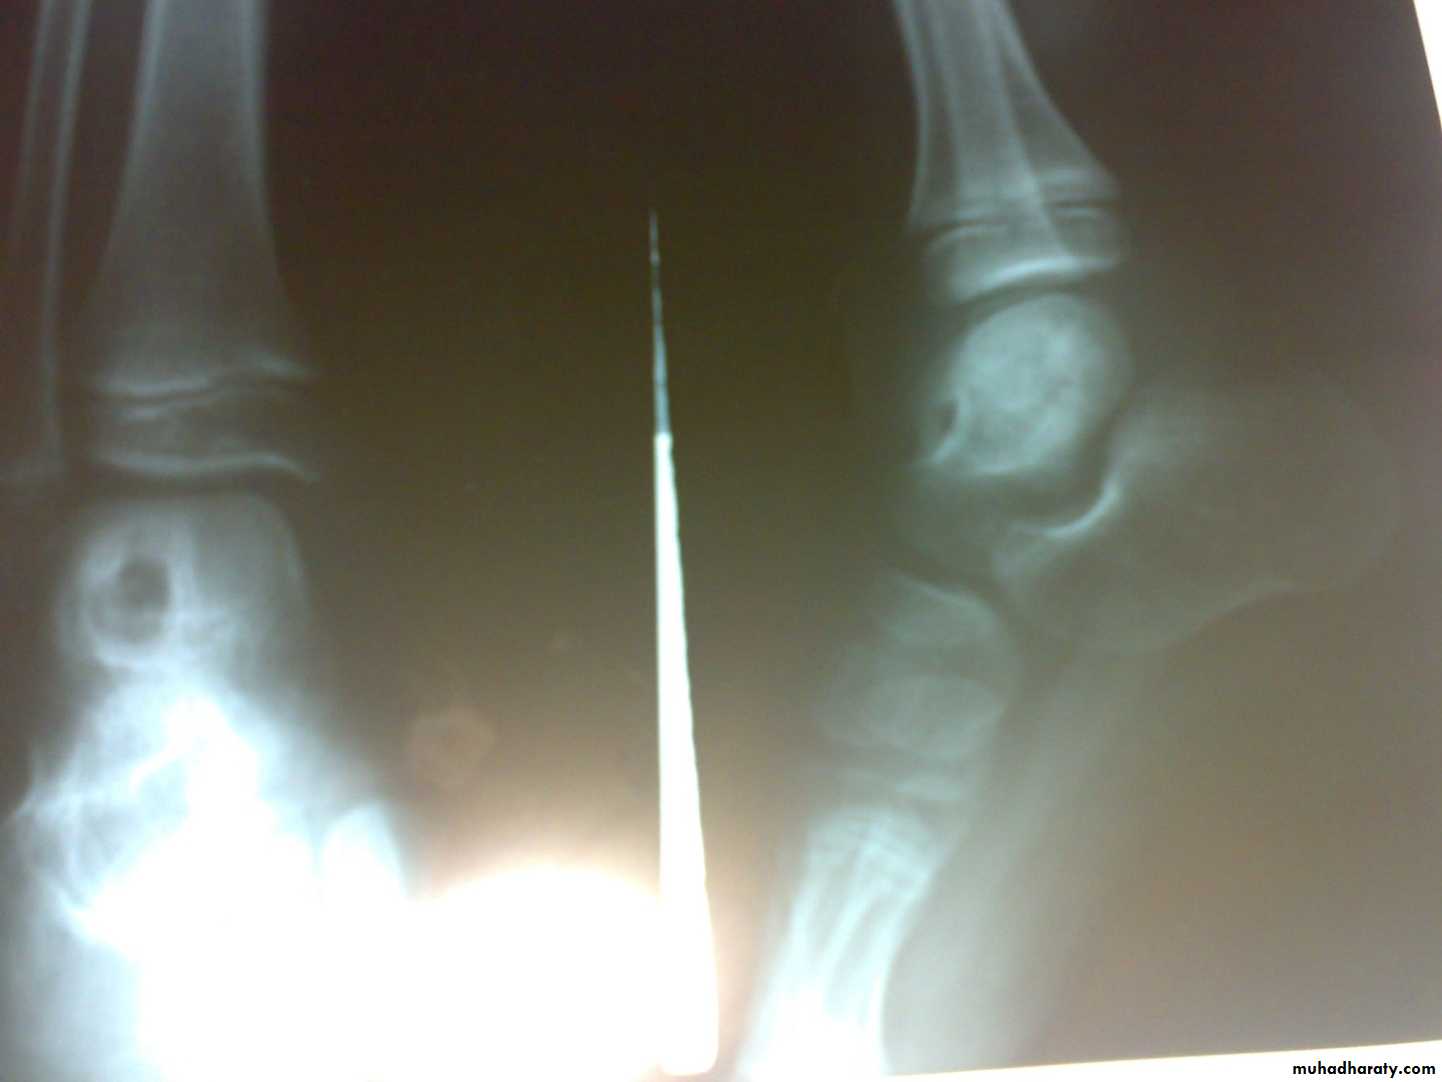

Radiological features

early changes:

Soft tissue swelling, Periarticular osteoporosis

Loclized osteoprosis (Bone ends ‘washed – out’ or localized decalcification ).

Narrowing and irregularity of the articular ends.

Late changes:

Erosions of the subarticular cartilage.

cystic changes appeared.